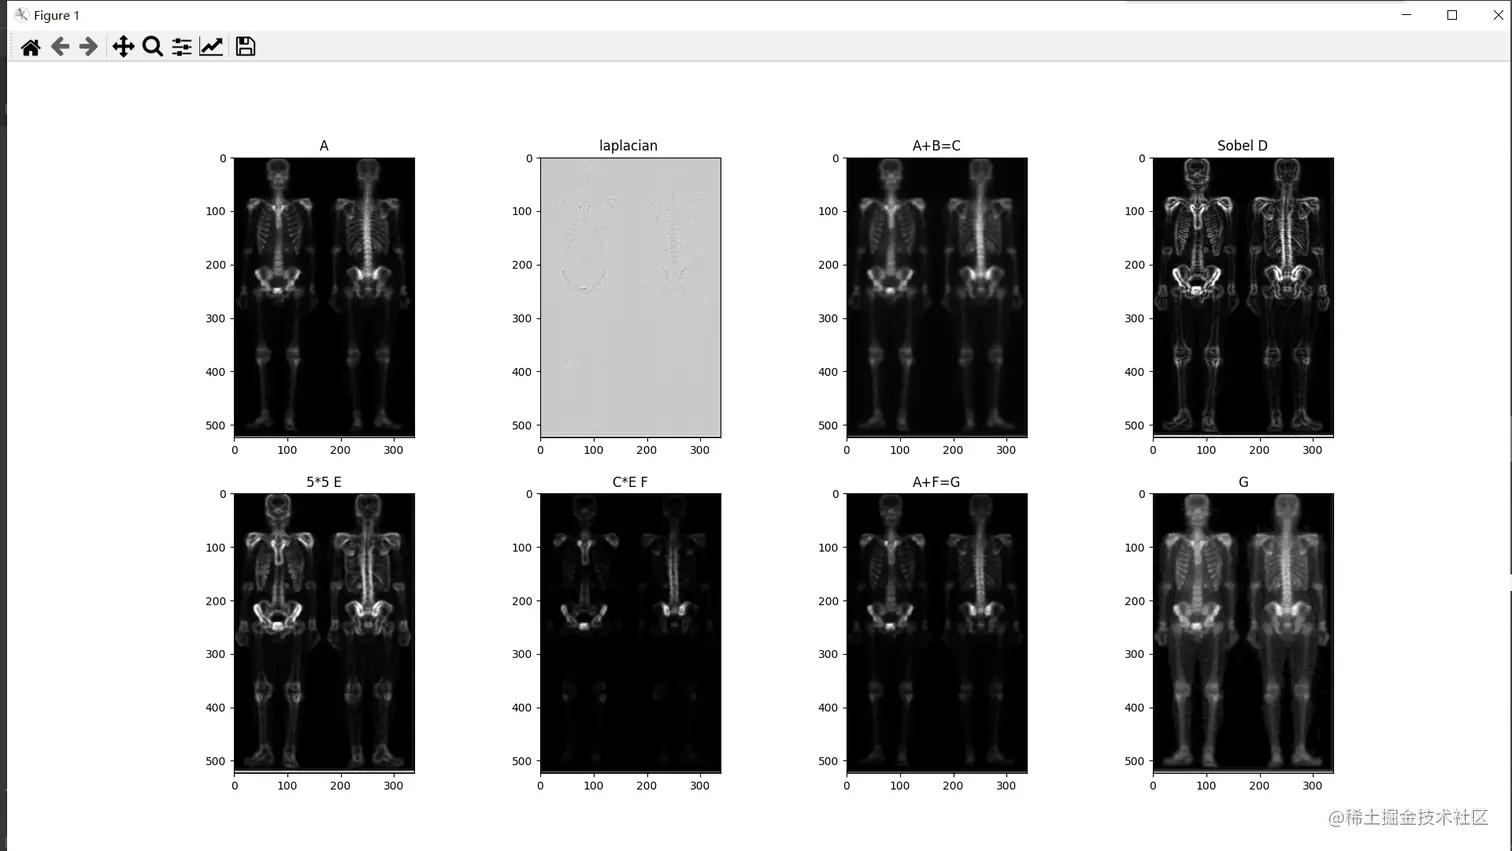

混合图像增强 以人体骨骼图像为例

运行结果